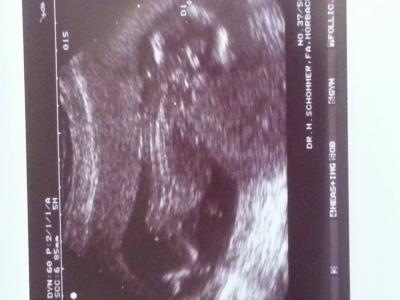

Huhu ihr Lieben War ja gestern Abend beim Frauenarzt. Baby geht es gut. Ist sehr aktiv. Ist mittlerweile 9 cm groß. Entwickelt sich super. Outing war nicht möchlich. Arzt hat noch gründlcih nach dem Herz geschaut (weil meine Tochter ja Herzkrank ist) aber bis jetzt keine Auffälligkeiten. Ist alles in bester Ordnung :-) Bin schon froh :-)

Bild zu Frauenarztbericht von gestern - Forum für Oktober - Mamis

Huhu!! Herzlichen Glückwunsch! Wahnsinn ist "es" schon groß! Die zeit vergeht sooo rasend schnell!! Freut mich das es euch beiden so gutgeht! Wie geht's dir gesundheitlich denn? Mal unter uns, is das da ein Fuß oder ein Zipfel???;) Gaaaaanz liebe Grüße Angie mit Mia

Das hört sich ja fabelhaft an. Und macht sich ja ganz schön lang in deinem Bauch. :-D Sorry, hat du bestimmt schonmal irgendwo geschrieben, ist der Herzfehler deiner Tochter sehr schwerwiegend? Was hast du für ein Gefühl, was "es" wird? Ich denke, der "Zipfel" auf dem US ist die Nabelschnur. ;-) LG elfchen PS: Wir denken auch gerade darauf rum, doch schon diesen Winter wieder in Produktion zu gehen. ;-) Bin mir aber unschlüssig, ob es nicht doch noch etwas zu früh ist und ein weiteres Jahr nicht besser wäre. Nur bei diesen Postings hier, wird mein Herz ganz weich. :-D

Ist die narbelschnur auf dem bild :-) Vom gefuhl her würde ich sagen wird ein Junge. .. Ich hab gar keine Beschwerden und bin top fit. Fuhl mich auch nicht schwanger. Hab aber auch keine zeit mich wirklich damit zu befassen, da franzi mich sehr fordert. Die ss läuft irgendwie so nebenbei. @elfchen Franziska hat eine arrythmie und eine tachykardie, bekommt 3x täglich einen beta-blocker und hat aber zum Glück keine Einschränkungen @sonja hab dir die liste am Montag per email geschickt. Hast du sie nicht bekommen?